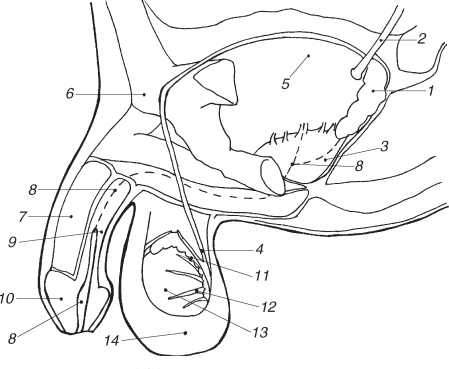

Мужские половые органы

1 – семенной пузырек; 2 – выводной проток; 3 – простата; 4 – семявыносящий проток; 5 – мочевой пузырь; 6 – лобковая кость (срез); 7 – кавернозное (пещеристое) тело полового члена; 8 – мочеиспускательный канал; 9 – кавернозное тело уретры; 10 – головка полового члена; 11 – придаток яичка; 12 – семенные канальцы; 13 – яичко; 14 – мошонка